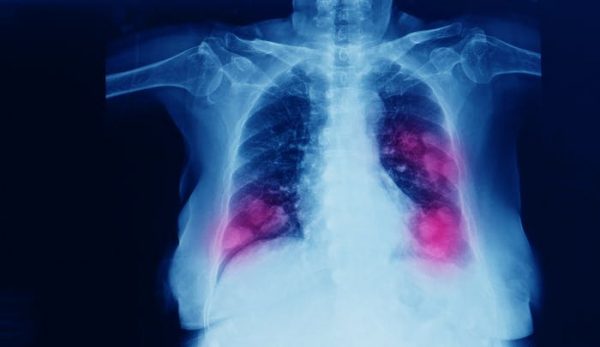

El paso del tiempo lo cambia casi todo menos la principal causa de cáncer en el mundo, que en las últimas décadas ha sido el cáncer de pulmón. Solo en España se diagnostican más de 30 000 casos cada año, y la supervivencia a cinco años apenas alcanza el 20 %. Parte del problema es que los tumores suelen detectarse tarde y que los tratamientos, incluso los más novedosos, acaban perdiendo eficacia.